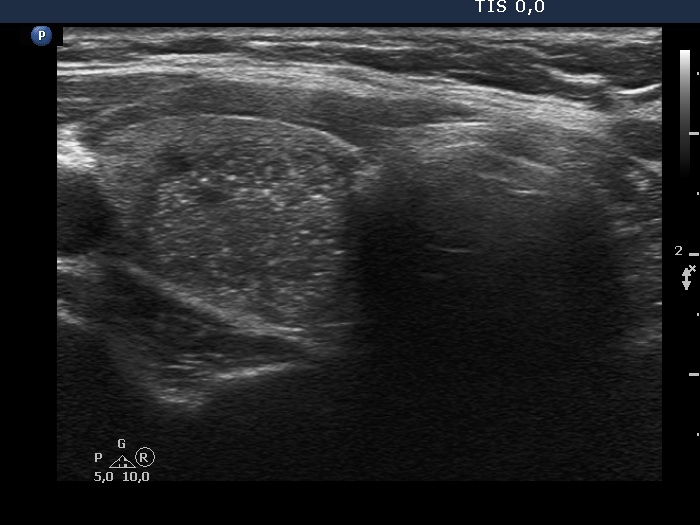

Ultrasonography. The thyroid was echonormal. There was a hypoechogenic nodule in the right lobe. The nodule had numerous punctate echogenic granules.

The echogenic figures are very difficult not to interpret as microcalcifications. Nevertheless, thorough analysis reveals that some of the bright granules has a short tale, and great proportion of these figures are related to ventral tiny hypoechoic areas, probably cysts. Moreover, there are not only echogenic granules but also short echogenic lines within the nodule. Taking all in all, these echogenic figures are very suspicious being microcalcifications.